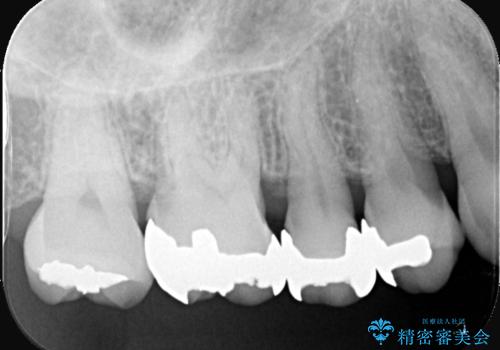

- 左上奥歯に入っている金属の詰め物(メタルインレー)の見た目を改善したいという主訴でご来院されました。お口の中の金属をなくしたいという患者様のご希望を踏まえ、天然歯に近い色と質感を持つセラミックインレーに交換する治療計画を立案。これにより、見た目の改善だけでなく、金属アレルギーのリスクを排除したメタルフリーの環境を実現することを目指しました。

治療では、まず古い金属のインレーを慎重に取り外しました。金属の下に隠れていた虫歯の再発がないかを確認し、歯を丁寧に形成。その後、精密な型取りから患者様の歯の色に合わせたオーダーメイドのセラミックインレーを作製しました。セラミックは、自然な光の透過性を持つため、周囲の歯と区別がつかないほどの美しい仕上がりとなります。適合性の高いセラミックインレーを装着することで、再発のリスクを抑えつつ、長年のコンプレックスだった銀歯がなくなり、笑顔でも気にならない自然な奥歯を取り戻していただけました。